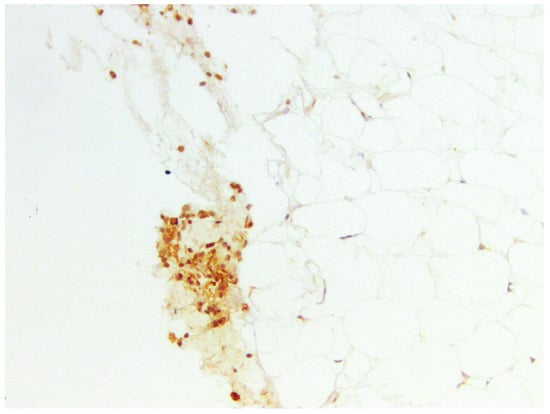

3.3.1. CD44

3.3.2. CD133

| % of Expression | CD44, Amount of Samples | Min Age | Max Age | Mean Age |

|---|---|---|---|---|

| 10 | 2 | 19 | 19 | 19.0 |

| 5 | 11 | 21 | 38 | 29.1 |

| 1 | 14 | 21 | 37 | 27.3 |

| 0 | 3 | 33 | 42 | 37.7 |

| % of Expression | CD133, Amount of Samples | Min Age | Max Age | Mean Age |

| 5 | 8 | 25 | 38 | 29.5 |

| 1 | 9 | 21 | 34 | 26.6 |

| 0 | 11 | 21 | 42 | 30.7 |